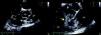

Transthoracic and transesophageal echocardiography revealed a restrictive subpulmonary ventricular septal defect (VSD) and infundibular pulmonary stenosis (Figure 1 and Video 1), with multiple vegetations related to the VSD involving the right coronary cusp of the aortic valve and protruding into the right ventricular outflow tract (RVOT) (Figure 2 and Videos 2 and 3). Vegetations were also observed adhering to the pulmonary valve and the pulmonary artery wall, probably due to jet lesion (Figure 3 and Video 4). A diagnosis of infectious endocarditis was made and the patient underwent surgery for removal of the vegetations (Figure 4), VSD closure, enlargement of the RVOT and pulmonary valvuloplasty without use of prosthetic material. His postoperative course was good, with no significant residual lesions, and there were no signs of heart failure or recurrence of endocarditis after two years of follow-up.